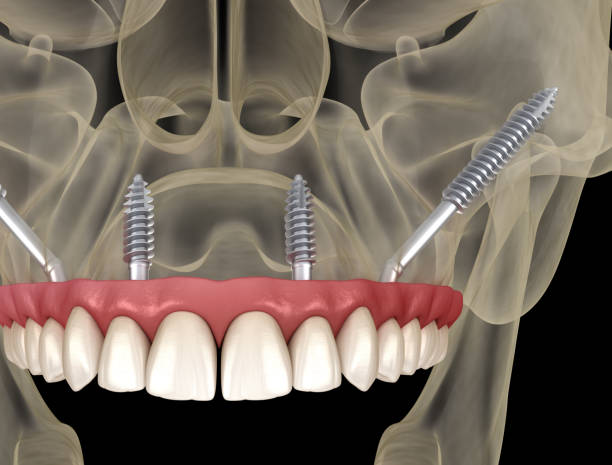

Advanced Procedures: Bone & Sinus Grafting for Dental Implants

Maintaining a healthy and beautiful smile is a lifelong endeavor, and at times, it might require advanced dental procedures. At Carlsbad Dental Associates, we are committed to providing our patients with comprehensive dental solutions, including bone and sinus grafting for dental implants. Led by the highly experienced Dr. Edward Adourian, our team is ready to assist […]